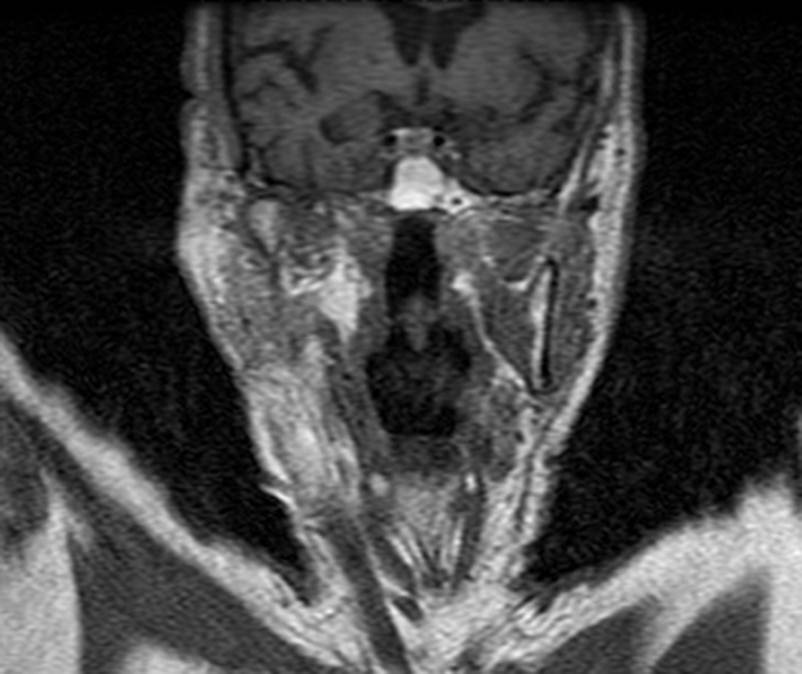

CT: Brain Atrophy

10 Years-Normal Gyri             65 Years-Enlarged Gyri